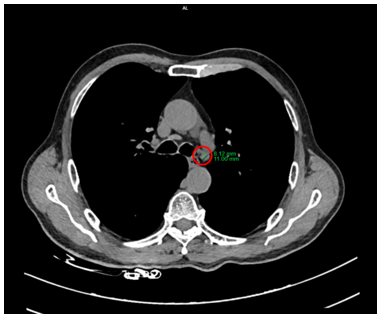

Hình 2: Hình ảnh hạch trung thất ở cửa sổ chủ phổi (vòng trong màu đỏ), kích thước 8x11mm, mất cấu trúc rốn hạch

Hình 5: Hình ảnh hạch trung thất ở cửa sổ chủ phổi đường kính 7mm trên CT (vòng tròn màu vàng) và PET/CT (vòng tròn màu đỏ) tăng chuyển hóa FDG (SUVmax: 2,69)